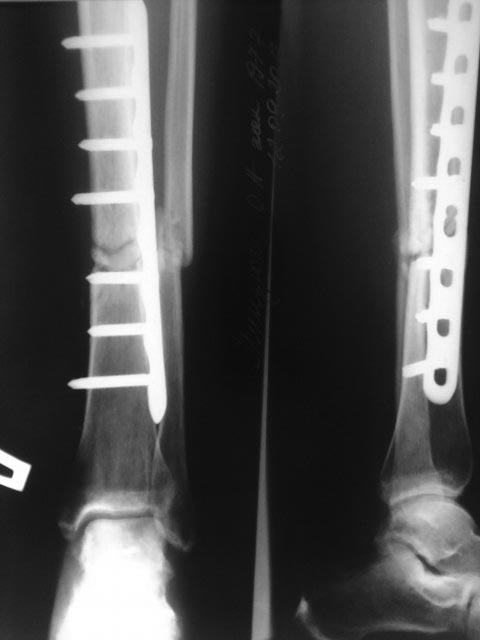

Здравствуйте! Спасибо за предоставленные снимки! Если судить по снимкам, то перелом сросся (костная мозоль со всех сторон). Необходима трансформация (уплотнение) костной мозоли, а для этого нужны нагрузка и время. Удаление пластины освободит наружный кортикал и распределит нагрузку равномерно по всей окружности кости. Что касается аутопластики, то она не показана при гипертрофическом псевдоартрозе. Ещё раз спасибо!

По данным рентгенограммам - перелом сростается. Исключить сомнения - сделать МСКТ. Если на МСКТ - данных за ложный сустав нет, то удалить металлоконструкцию и пользоваться ортезом на голень до достижения более прочной костной мозоли по данным контрольных R-грамм.

Еще бы понятно околосуставной, но зачем диафизарный перелом tibia в наши дни синтезировать пластиной?

Периостальная спайка вроде там все-таки есть. Наверно, ничего не надо делать. Или далить ближайшие к перелому винты, чтобы не было концентрации напряжений.

Доброго дня, Олег... Случай интересный. Непонятно расположение пластины( наружная установка имеет конкретные узкие показания) и выбор и количество винтов. В тактике, скорее соглашусь с доктором Челноковым, но если не уберете ближайшие к зоне перелома блокированные винты, скорее всего произойдет перелом конструкции. Уберите, может перелом срастется в условиях относительной стабильности. А пластика в этом случае, конечно не показана...